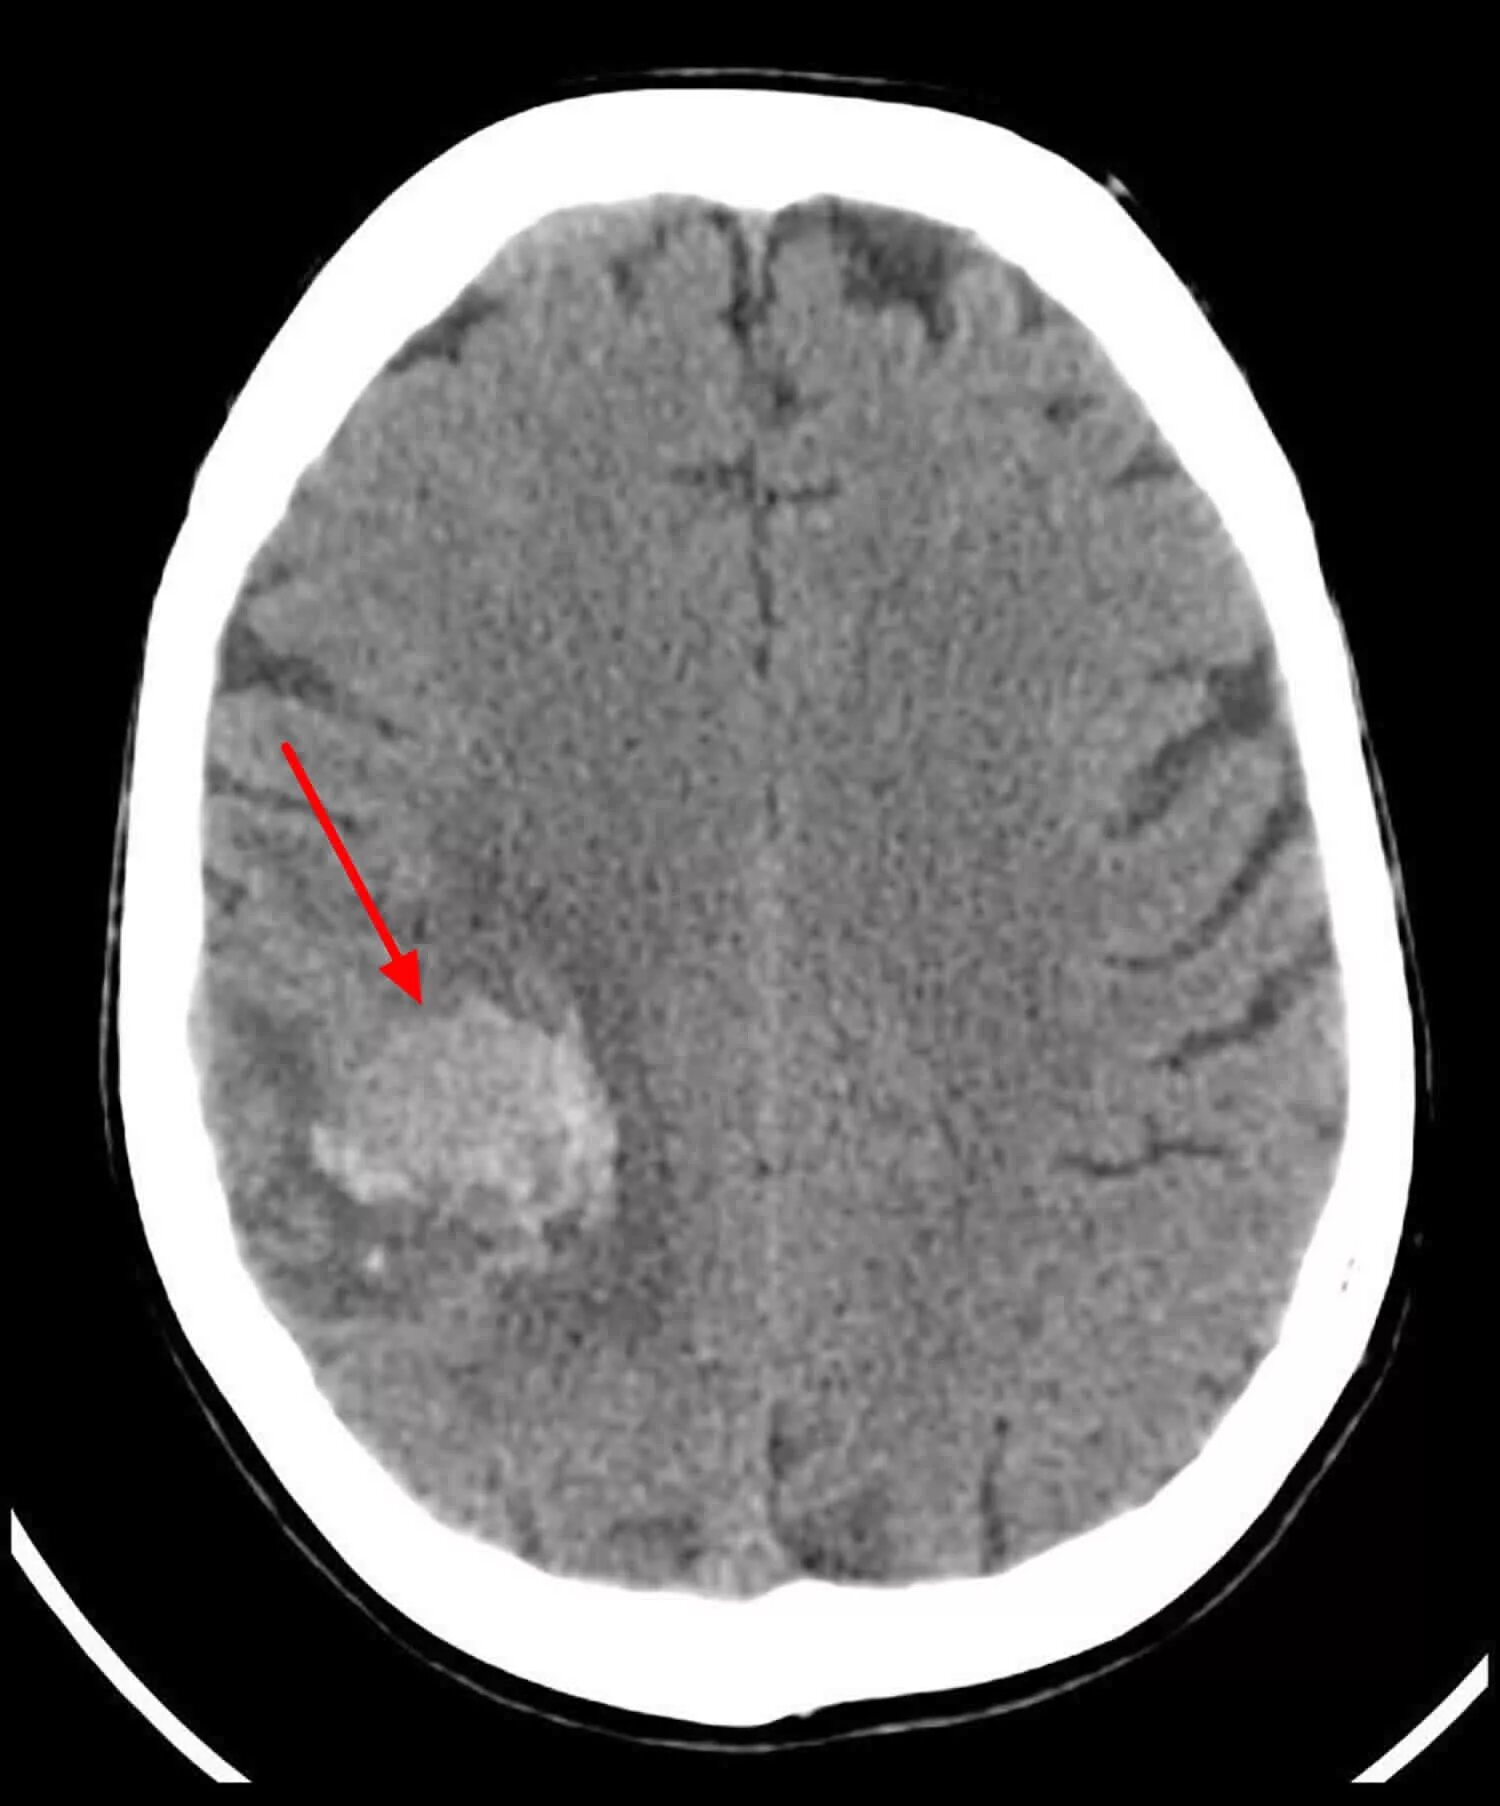

Метастазы головного мозга кт